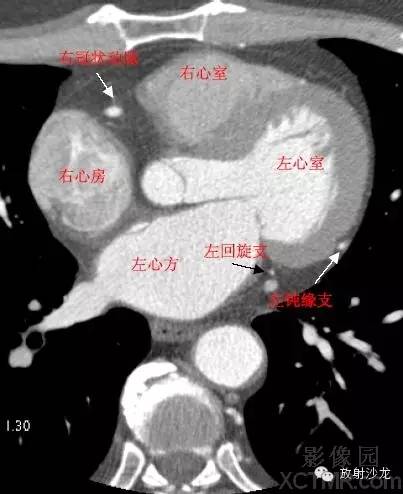

LA -Left Atrium左心房

RA -Right Atrium右心房

LV -Left Ventricle左心室

RV -Right Ventricle右心室

LCX -Left Circumflex Artery左回旋支

LMB -Left Obtuse Marginal Branch 左边缘支(钝缘支)

RCA -Right Coronary Artery 右冠状动脉